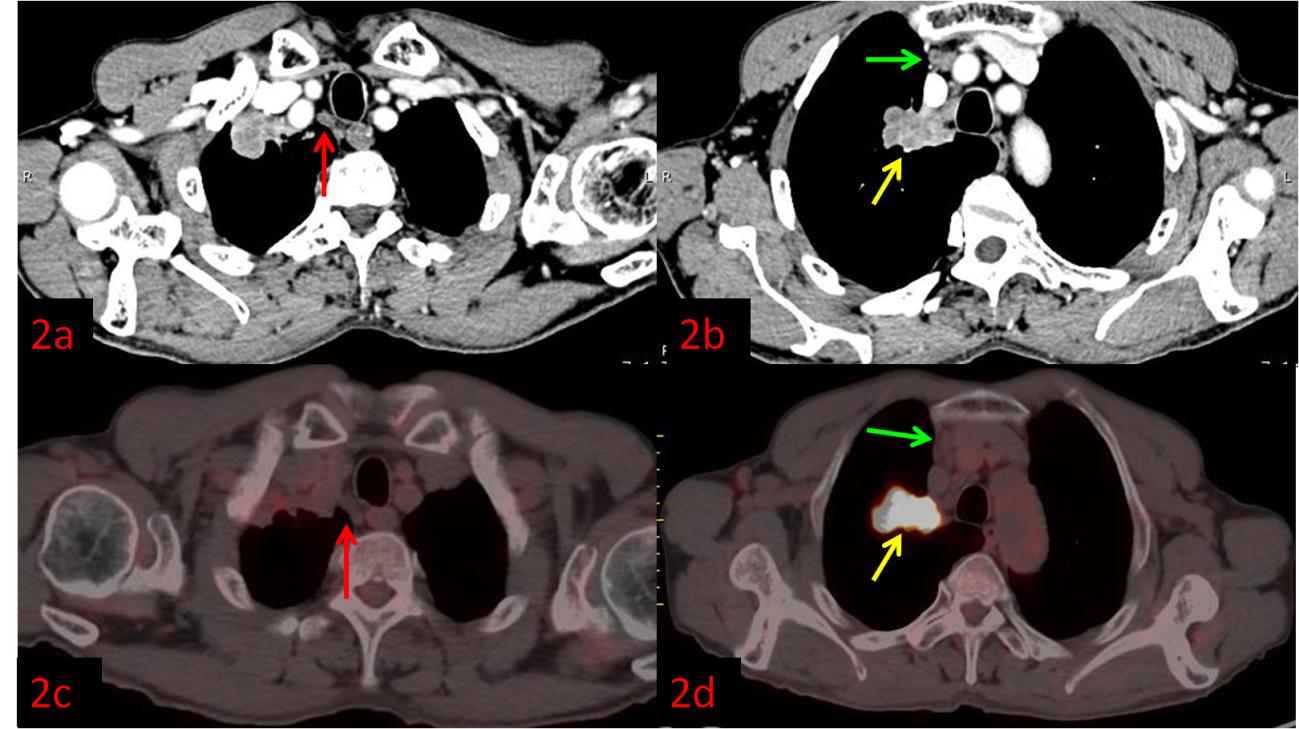

例2:老年男性,右肺上葉病變(黃箭)。強(qiáng)化CT示右上縱隔多發(fā)腫大淋巴結(jié),不均勻強(qiáng)化,考慮轉(zhuǎn)移(圖2a紅箭、2b綠箭),初步分期為ⅢB,無法行手術(shù)根治。而PET/CT顯示淋巴結(jié)FDG代謝不高,考慮良性(圖2c紅、2d綠箭),患者分期降為ⅡB,于是進(jìn)行了根治性手術(shù)。術(shù)后病理:右肺上葉鱗狀細(xì)胞癌,淋巴結(jié)均未見轉(zhuǎn)移。